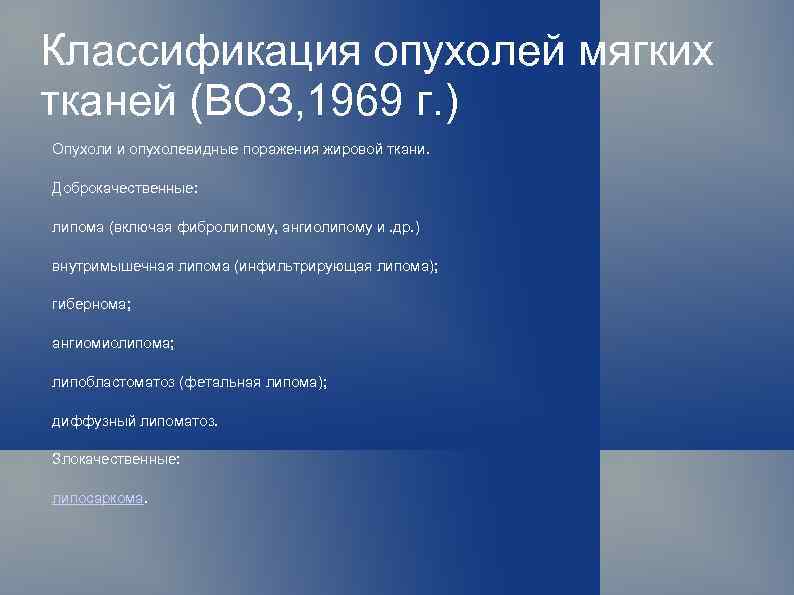

Классификация опухолей мягких тканей (ВОЗ, 1969 г. ) Опухоли и опухолевидные поражения жировой ткани. Доброкачественные: липома (включая фибролипому, ангиолипому и. др. ) внутримышечная липома (инфильтрирующая липома); гибернома; ангиомиолипома; липобластоматоз (фетальная липома); диффузный липоматоз. Злокачественные: липосаркома.